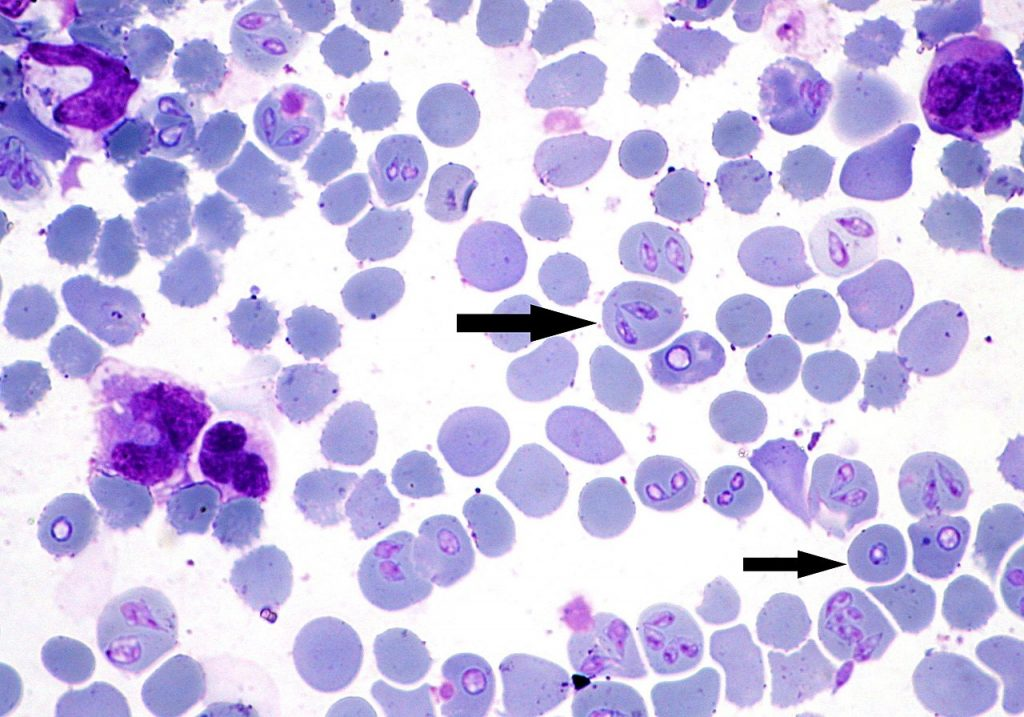

babesia sp stadia schizogonii krwinkowej

babesia sp stadia schizogonii krwinkowej